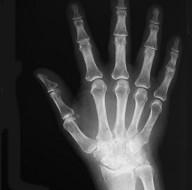

问题 女,56岁,手指关节肿胀,疼痛,僵硬,结合影像图像,选择最可能的诊断 ( )

选项 A、Reiter综合征 B、骨囊肿 C、类风湿关节炎 D、痛风性关节炎 E、关节结核

答案 C